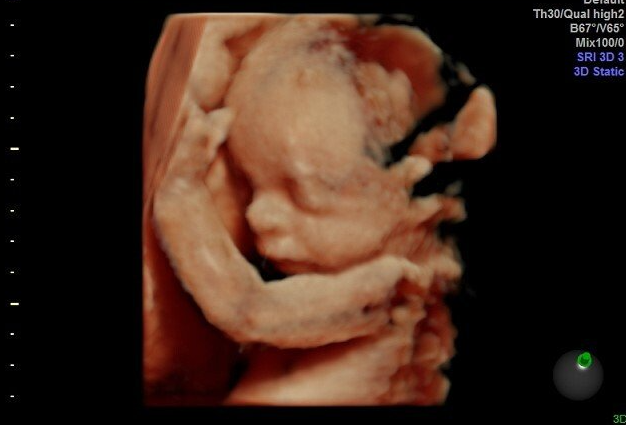

Gallery